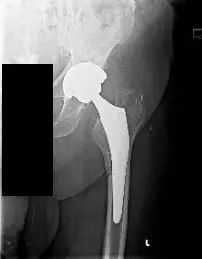

Preoperative X-ray of the Left Hip AP view showing a periprosthetic femoral fracture (minimally displaced along the medial aspect of the proximal femoral shaft) with subsidence of the stem.